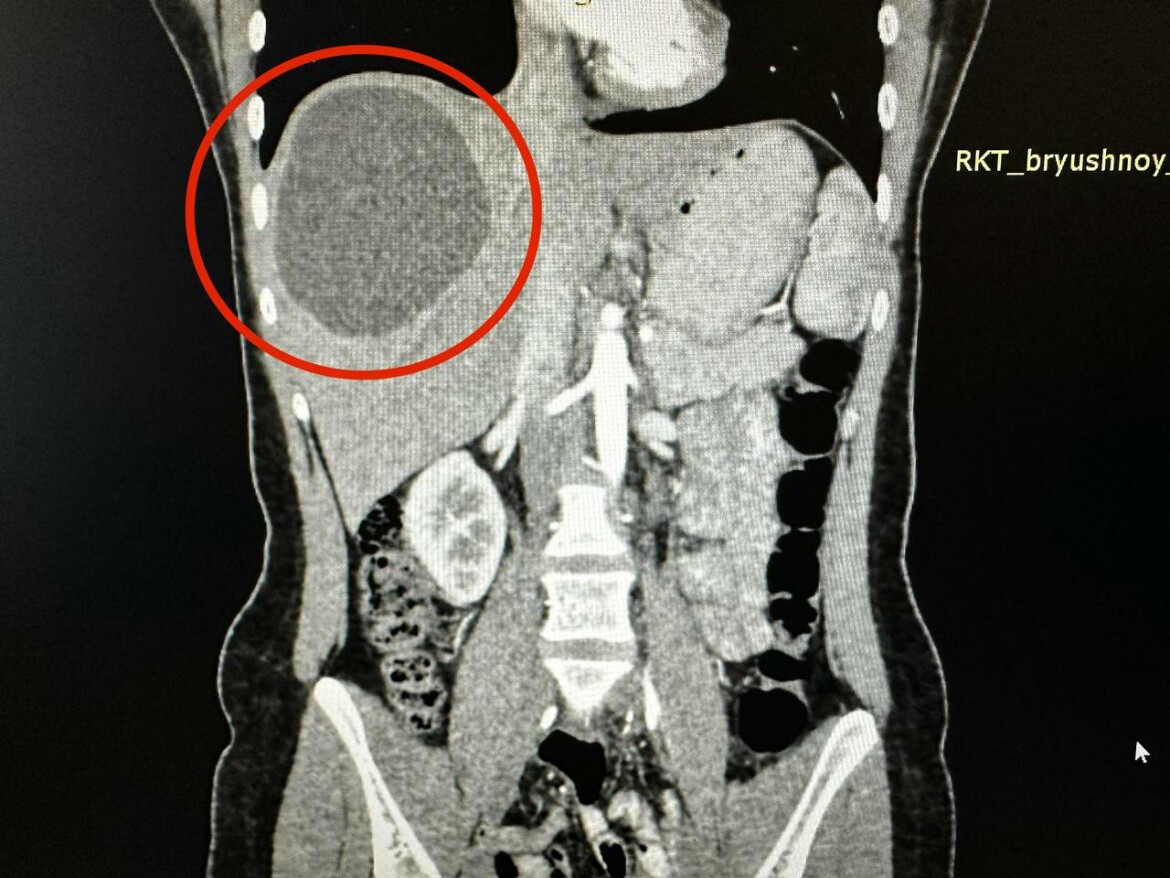

Огромный эхинококк убрали врачи РКБ Татарстана у 19-летней девушки

Кисту эхинококка, которая занимала треть печени, удалили врачи Республиканской клинической больницы Татарстана у 19-летней девушки.

С сильными болями в животе она обратилась к врачам несколько месяцев назад. Во время обследований медики обнаружили паразитов в печени, которые образовались в кисту размером 20 на 15 см.

Фото: © пресс-служба РКБ Татарстана

Из-за того, что паразиты поразили здоровые ткани печени, хирургам отделения хирургии №2 пришлось убрать практически треть органа.